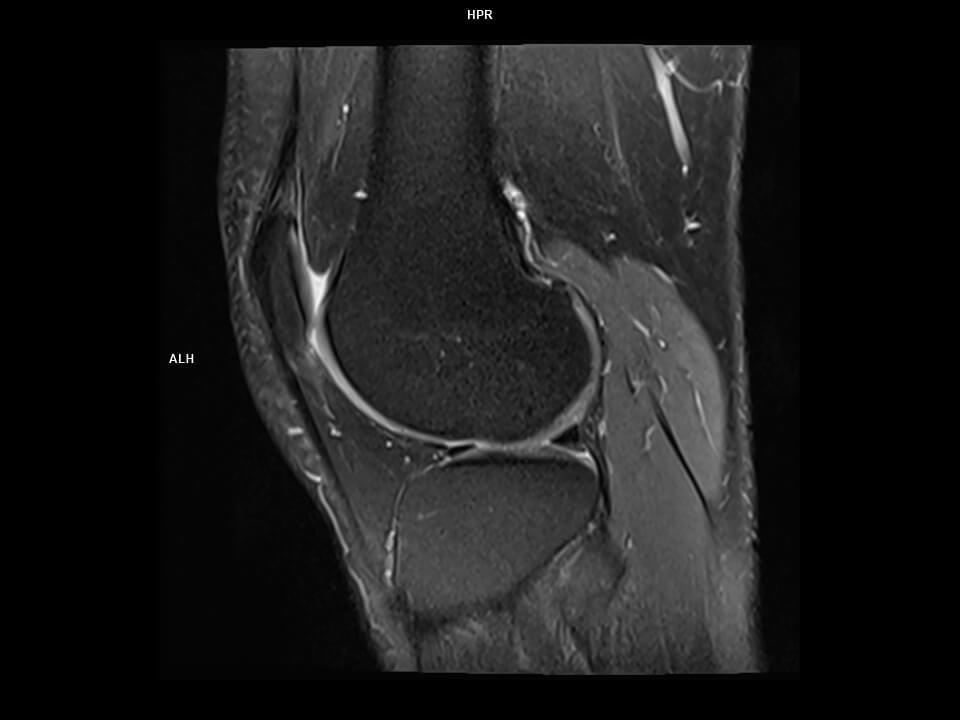

Sagittal PD tse FS-MAGNETOM Altea

Sagittal PD tse FS-MAGNETOM Altea/Coil-Knee18/Resolution-576/Scan Time-0:46/Aceleration-s2